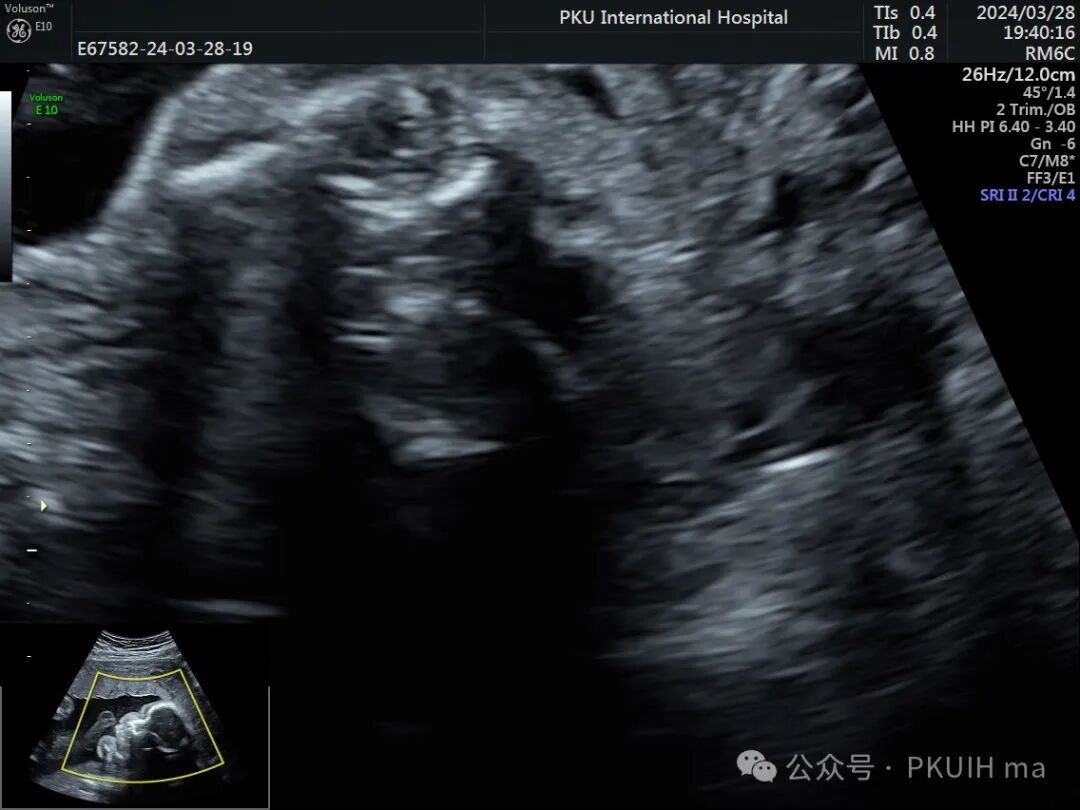

实时动态观察双眼发育不对称,右眼小;两侧眼球内晶状体、玻璃体均可见,右侧晶状体小,晶状体后缘玻璃体内见不规则的高回声区。

综合以上图像初步考虑为永存原始玻璃体增生症(PHPV)。